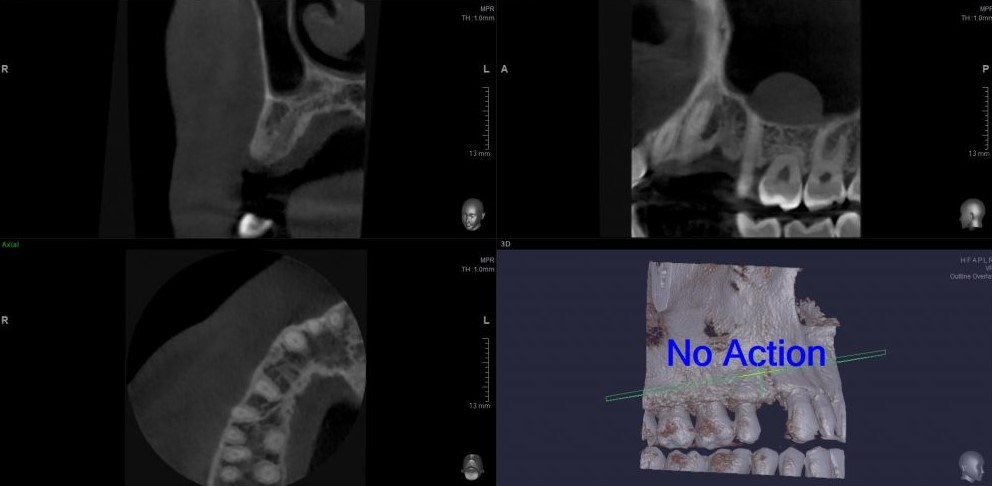

Помимо визуального осмотра

нам требуется провести рентгенологическое исследование. В данном случае простого ОПТГ (Панорамного снимка зубов) нам будет недостаточно. Потребуется КЛКТ (Конусно-лучевая компьютерная томография).

ОПТГ (Ортопантомограмма) — обзорный снимок зубочелюстной системы. Данный снимок является плоскостным, а значит происходит наложение каждой детали снимка послойно друг на друга. Следовательно, рассмотреть объект исследования, в частности место планируемой имплантации, во всех плоскостях, под иным углом или другой проекции невозможно.

КЛКТ (Конусно-лучевая компьютерная томография) — 3D объемный снимок, напротив дает нам такую возможность.

В данном случае, объёмов костной ткани достаточно для стабилизации оптимального по размеру имплантата, а качество десны делает возможным формирование эстетического контура без дополнительных процедур: